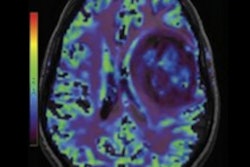

Functional MRI (fMRI) reveals that a brain region in the superior temporal sulcus (fSTS) is crucial for processing and making decisions about visual information and could provide information to treat visual conditions arising from stroke, according to a December 17 study in Neuron.

Researchers directly measured the firing of fSTS neurons in the areas of monkeys' brains as revealed by fMRI. The research team was led by Richard Krauzlis, PhD, chief of the National Eye Institute Section on Eye Movements and Selective Attention, which is part of the U.S. National Institutes of Health.

The monkeys fixed their eyes on a dot straight ahead and either paid attention to or specifically ignored stimuli happening in their visual periphery. The superior colliculus was strongly triggered when the monkeys paid attention to the visual event and a large proportion of fSTS neuronal activity was dependent on the superior colliculus.

When Krauzli and his team dampened the superior colliculus, the fSTS neurons showed less distinction between stimuli that the monkeys paid attention to versus what they ignored, meaning the fSTS depends on the superior colliculus to mark which stimuli are important and which are not.